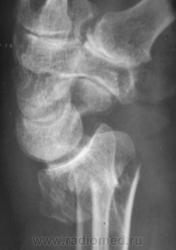

Случай 2.  Пациент направлен врачом хирургом на рентгенографию лучезапястного сустава.

Случай 3. Пациент направлен врачом хирургом на рентгенографию лучезапястного сустава.

А вот по-поводу второго случая: перелом луча в "типичном" месте, только вот смущает ладьевидная кость - какая-то она патологическая, имеется участок разряжения костной ткани в проекции головки кости или я ошибаюсь?